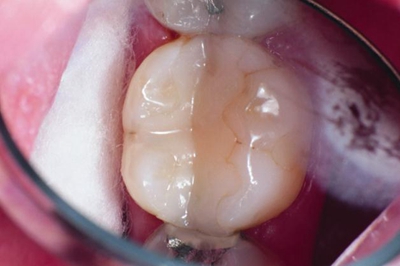

用Consepsis Scrub或拋光膏清潔舊修復(fù)體表面和鄰近釉質(zhì)。沖洗、酸蝕15秒,徹底沖洗,空氣吹干。

4年前制作的復(fù)合樹脂舊修復(fù)體(用PermaSeal后)。